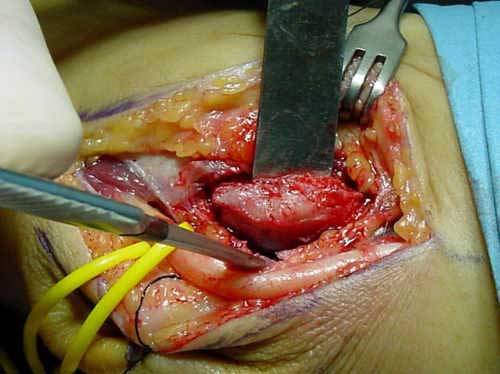

Es importante comprobar una vez liberado el nervio que no se subluxa. (Fig. 5).

Fig. 3: Incisión Quirúrgica

Fig. 4: Liberación in situ del nervio

Fig. 5: Comprobación en flexión de la ausencia de subluxación del nervio